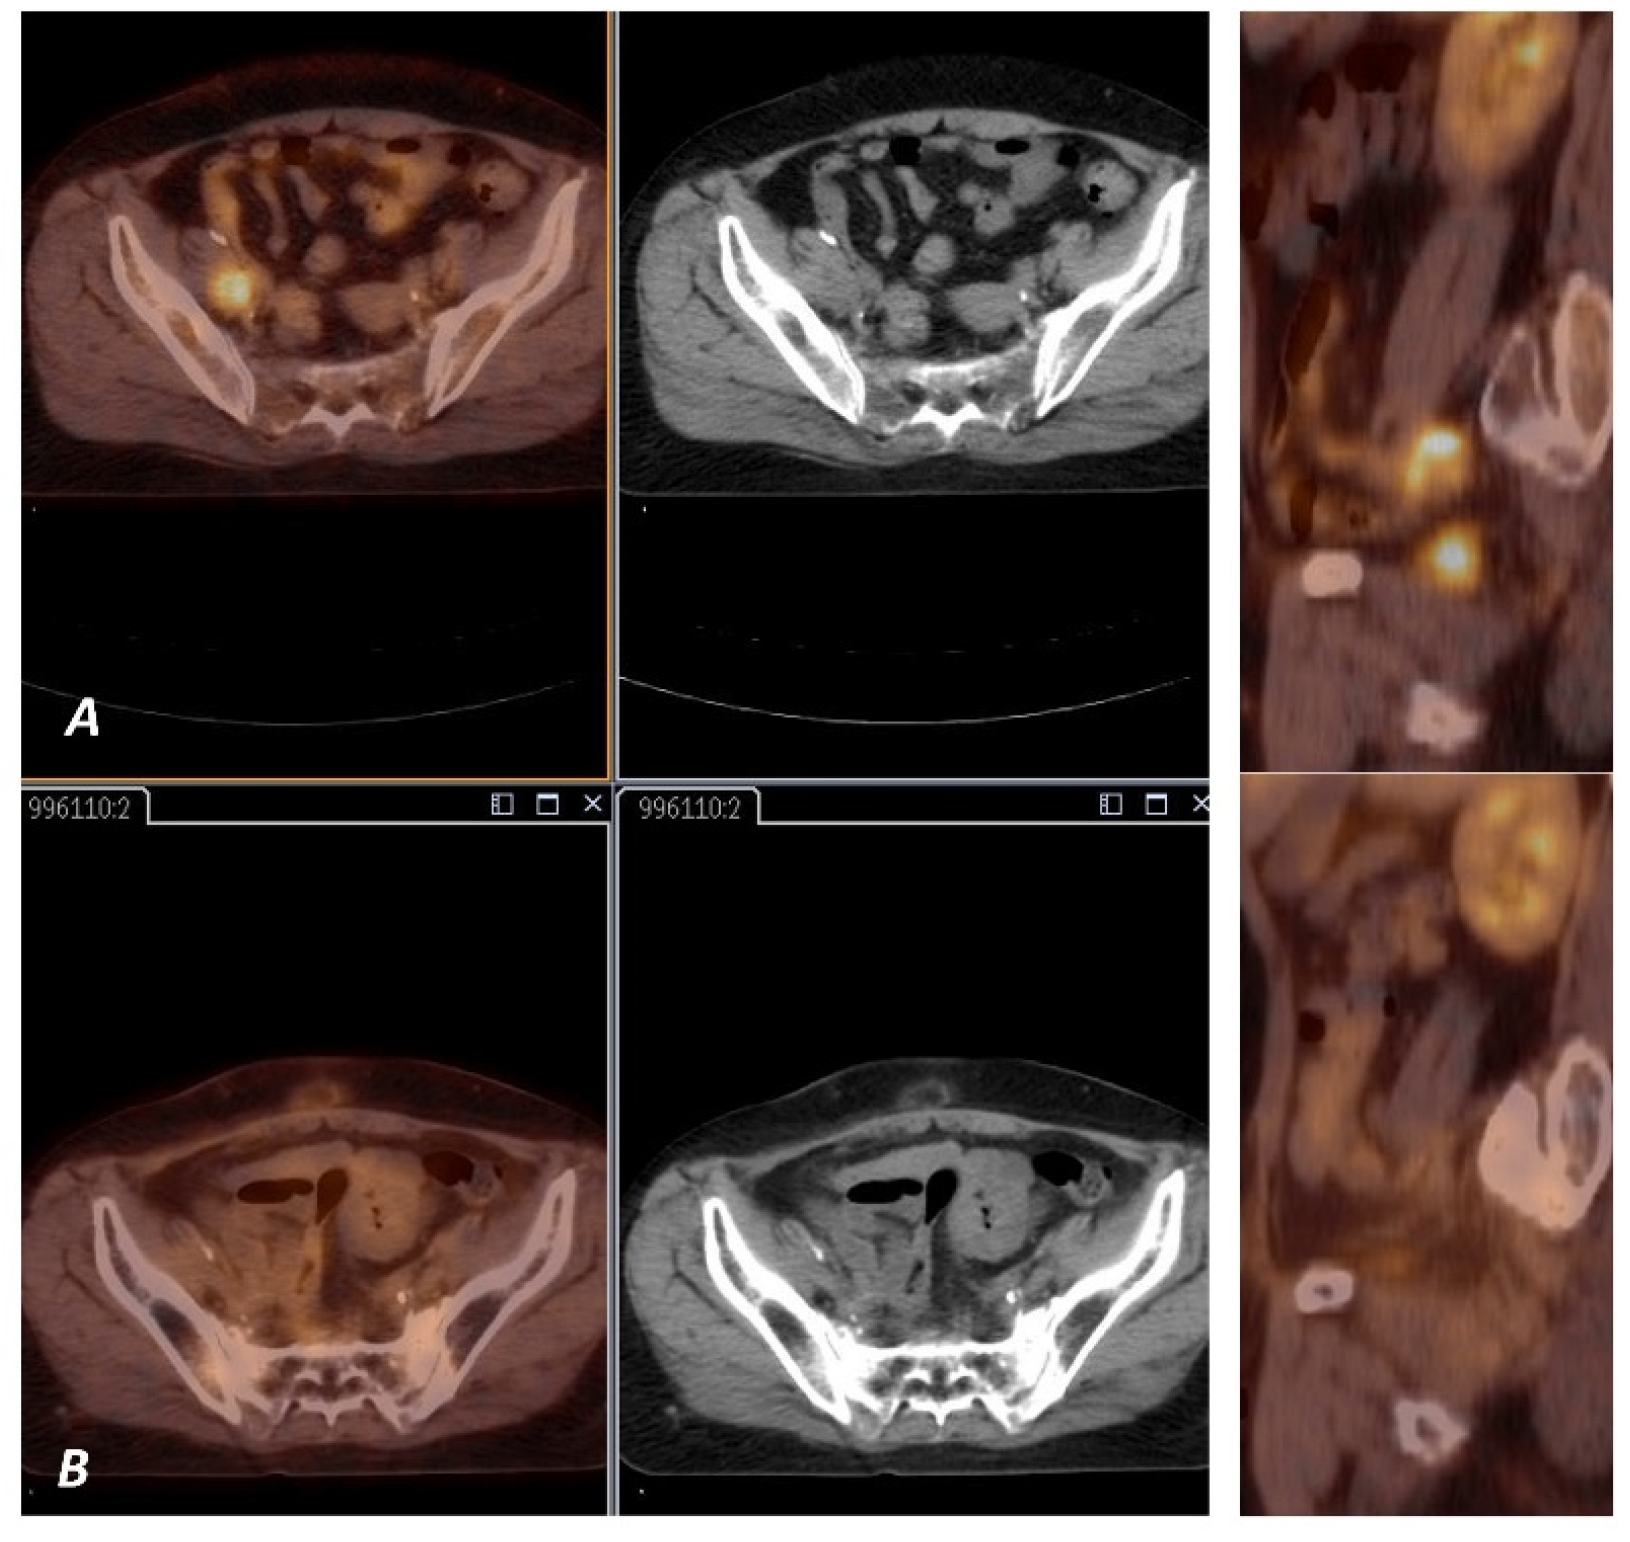

2.2. PET Imaging and Analysis